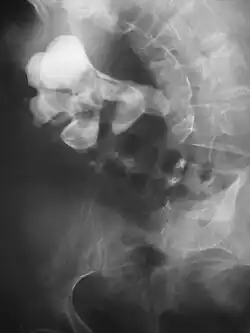

| Cálculo renal com 8 mm de diâmetro | |